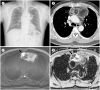

The mediastinum is the most prevalent site of extragonadal teratomas. Patients with mediastinal mature teratomas are usually young adults, and the condition does not show significant sexual differences. Mediastinal teratomas are mostly located in the anterior mediastinum. Patients are usually asymptomatic, although they can have several complications when the teratomas become large or rupture. Most mediastinal teratomas can be diagnosed using CT. Diagnosing ruptured or malignant teratomas is challenging because of their atypical clinical and radiological presentations. In this article, we describe various manifestations of mediastinal teratomas, with an emphasis on radiologic features.